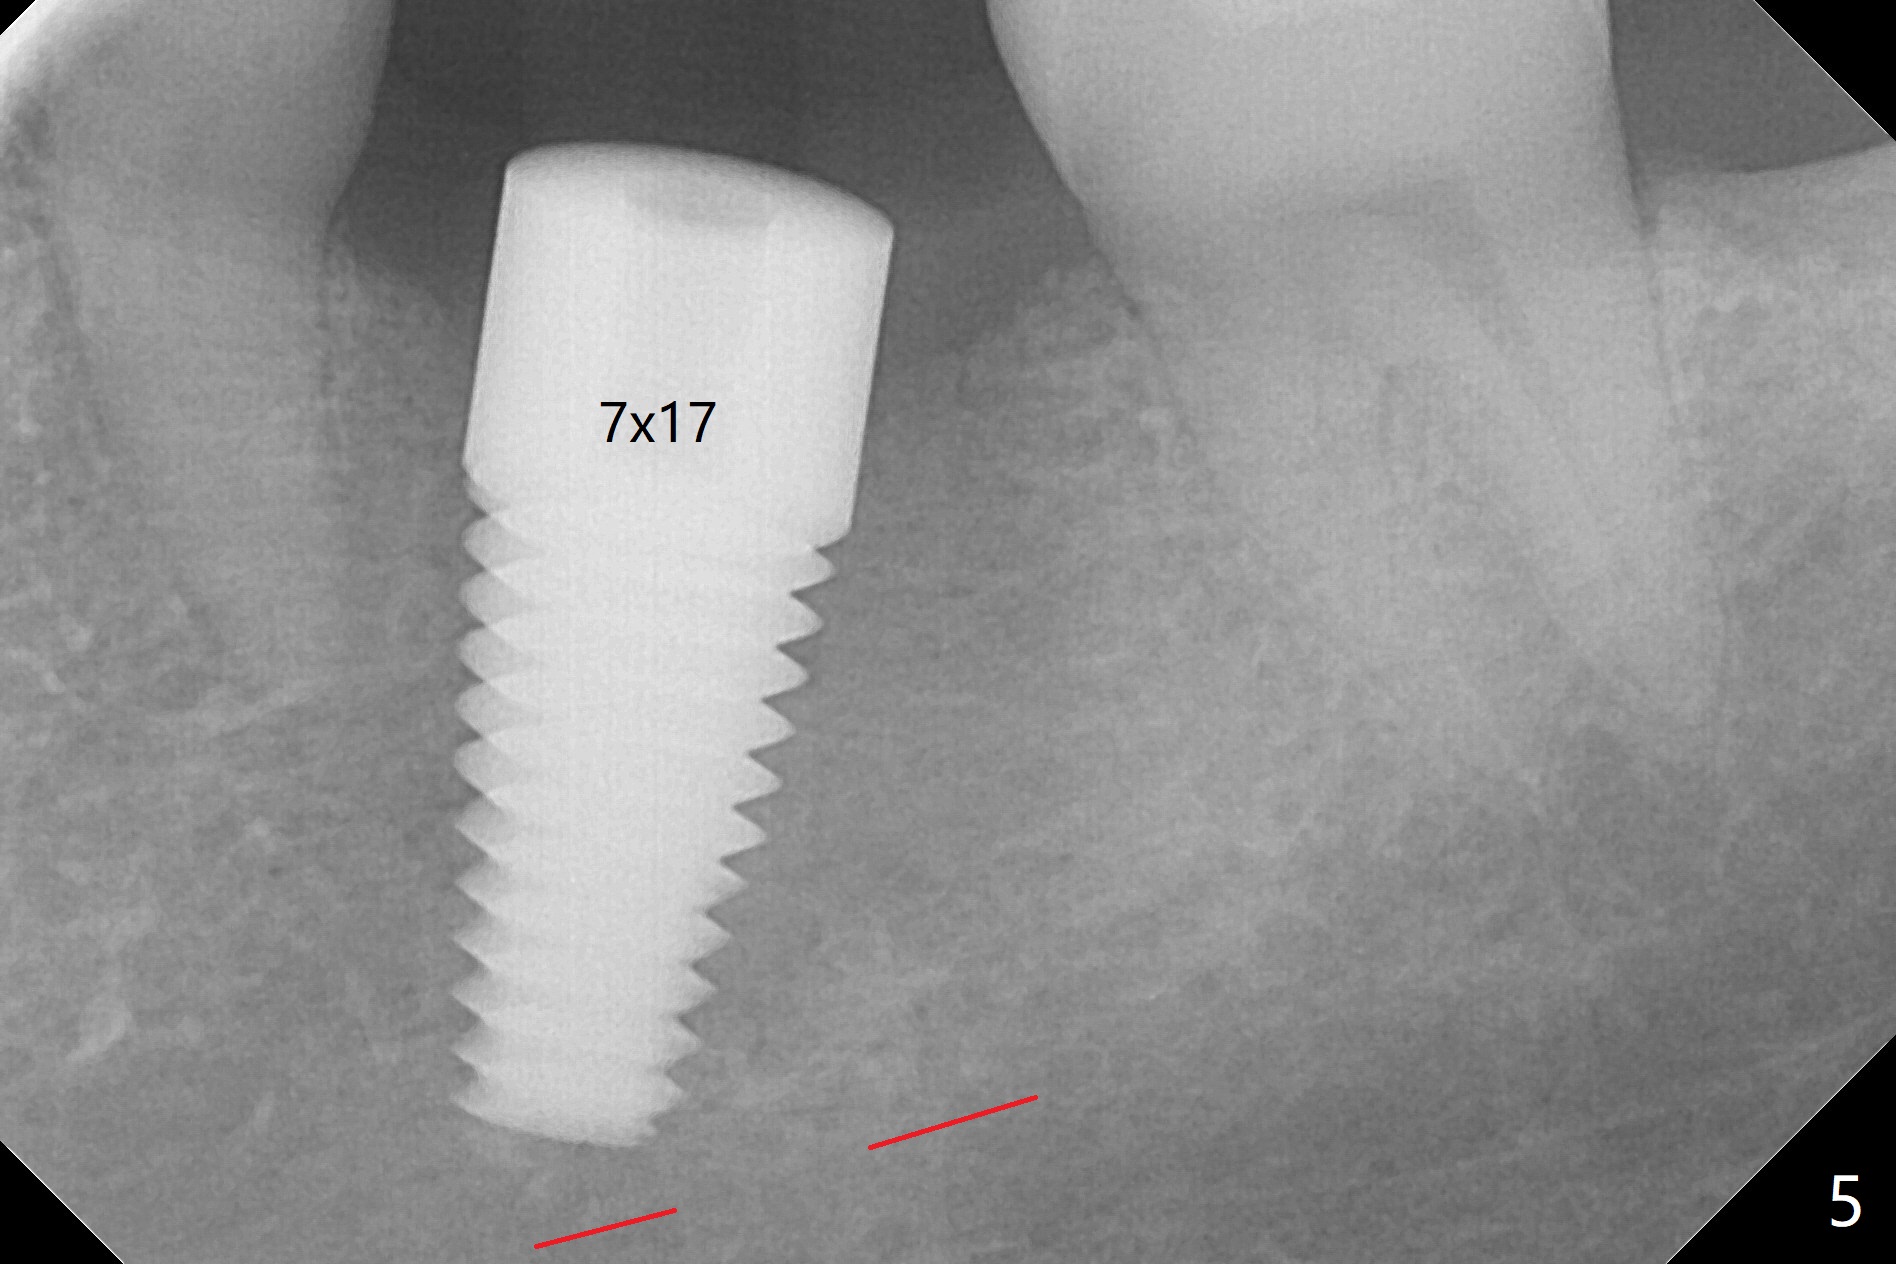

After 4.0x10 mm drill with 9 mm offset for 4.5x10 mm bone-level implant at #19, a 4.5x17 mm tissue level tap is inserted with apparently low torque (probably without reaching the depth). When a 4.5x14 mm tissue level implant is placed with high torque, a 4.5x7.3 mm drill is used for ~ 6.5 mm. The implant loses the primary stability with over-insertion (Fig.1). When an abutment is placed, the implant is critically loose. Mixture of autogenous bone, Osteogen and allograft is placed in the osteotomy. The implant regains stability with better placement level for restoration (Fig.2). In fact the bone density around the implant increases (Fig.2 *). For the first 7 days postop, the patient has to take Advil. When he returns for follow up 8 days postop (Fig.3), the pain decreases, while there is minor degree of lower lip paresthesia. Medrol Dose Pak and Tylenol III are prescribed. The implant is loose 24 days postop; after removal of the implant and apparently infected bone graft, a 7x14 mm dummy implant is inserted with <20 Ncm and 3-4 mm clearance (Fig.4). A longer dummy implant seems to improve stability (Fig.5). So does the definitive implant (Fig.6,7, 25 Ncm), but it is placed low. The gingiva looks healthy 13 days postop (2nd placement). A healing cap will be placed for restoration ~ 3 months postop. CT will be taken if the implant needs to be backed up to determine whether there is enough bone buccolingually. Due to coronavirus and prolonged placement of a healing abutment with poor oral hygiene, the buccal gingiva of the implant is erythematous 1 year postop (Fig.8 healing cap just removed) with bone loss (Fig.9,10 *). Sticky bone seems to be necessary. A 6x5 mm abutment with slots will be placed to hold periodontal dressing in place.